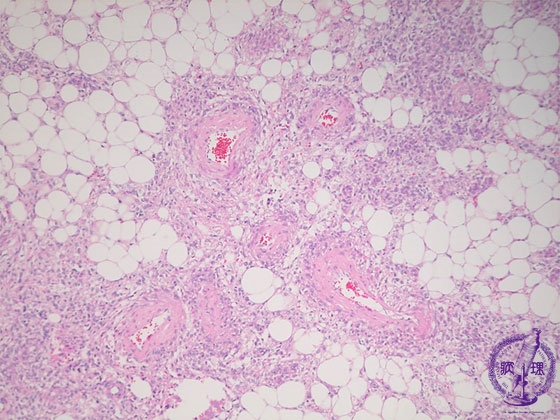

腎血管平滑筋脂肪腫(結節性硬化症)ミクロ像(HE中拡大)

ミクロ像(HE中拡大):腫瘍内では脂肪細胞、壁の肥厚を伴う血管、平滑筋細胞が認められる。